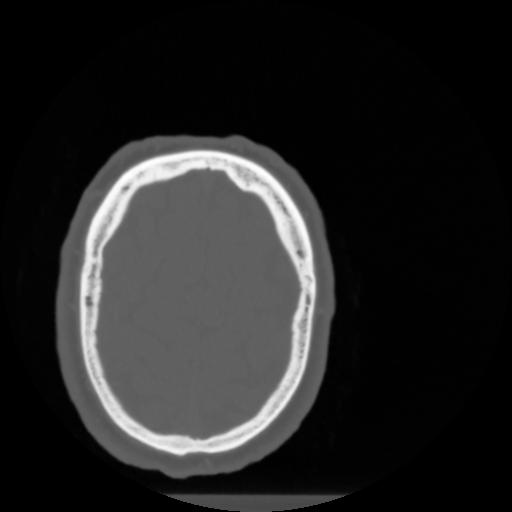

4 CEREBRO,,Vol,0.5,CEREBRO,,